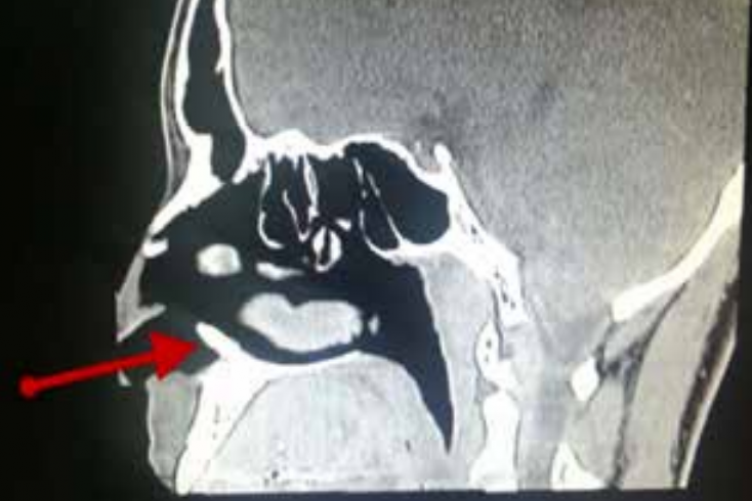

چنانچه لامینای دندان بیش از تعداد طبیعی جوانه های دندانی تشکیل شود، دندان اضافی را ایجاد می کند. طبق آمارهای موجود وقوع دندانهای اضافی کمتر از ۱۵ درصد است و آقایان دو برابر خانمها مبتلا می شوند. شایع ترین محل های بروز دندان اضافی در فاصله بین دندانهای پیشین مرکزی فک فوقانی و فک تحتانی است. دندانهای اضافی تا زمانیکه در نظم دندانهای طبیعی تغییری بوجود نیاورند فقط از طریق رادیوگرافی قابل تشخیص خواهند بود. بروز دندان اضافی در بینی نادر است، بخصوص اگر دندان مذکور دندان نیش باشد. در سال ۱۹۹۴ یک مورد دندان اضافه به شکل دندان پیشین در بینی گزارش شد و در ۱۰ سال اخیر فقط یک مورد دندان به شکل دندان نیش در بینی گزارش شده است. مورد بحث کودکی ۷ ساله بوده که در سال ۱۹۹۳ متعاقب ضربه با ناحیه صورت در دوران شیرخوارگی دچار این مشکل شده بود. ضربه مذکور منجر به بروز ناهنجاری دندانی به شکل نابجا قرار گرفتن نیش در بینی و فقدان دندان پیشین شده بود. معاینات دست جمعی کودکان برای تشخیص دندانهای اضافی و ممانعت از بروز عوارض احتمالی از جمله جابجایی دندانها و اتصال دندانهای فوق به سایر دندانهای طبیعی یا استخوان فک فوقانی و تحتانی توصیه می گردد. اخیراً هم خانمی ۳۳ ساله تهرانی با احساس توده ای تیز و سفت در کف حفره بینی به پزشک مراجعه می کند. در معاینه جسمی سفید، سفت با ظاهری شبیه با تاج دندان نیش، بدوت علامتی دال بر التهاب، آبسه، کیست و عفونت در کف بینی طرف چپ مشاهده می شود. وضعیت روی هم قرار گرفتن دندانها وتعداد آنها هم طبیعی بوده است. در بررسی رادیولوژیک دندان اضافی به خوبی قابل مشاهده بود که نهایتاً با جراحی از طریق شکاف داخل دهانی در ناحیه لثه ای - گونه ای فک فوقانی دندان اضافی با گوژ و چکش از داخل استخوان بطور کامل خارج می شود.